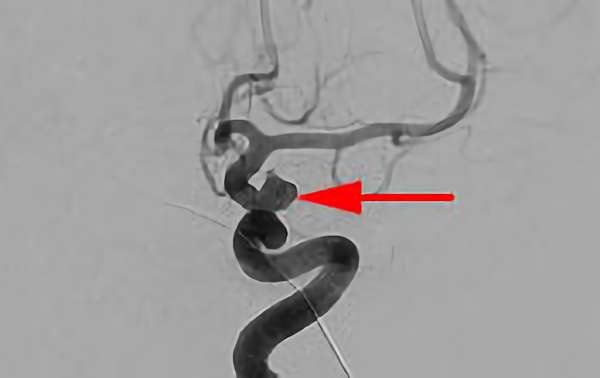

No.1631 手術中